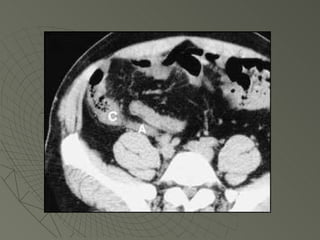

PLASTRON  APENDICULAR APENDICE CECAL

PLASTRON APENDICULARAPENDICE CECAL